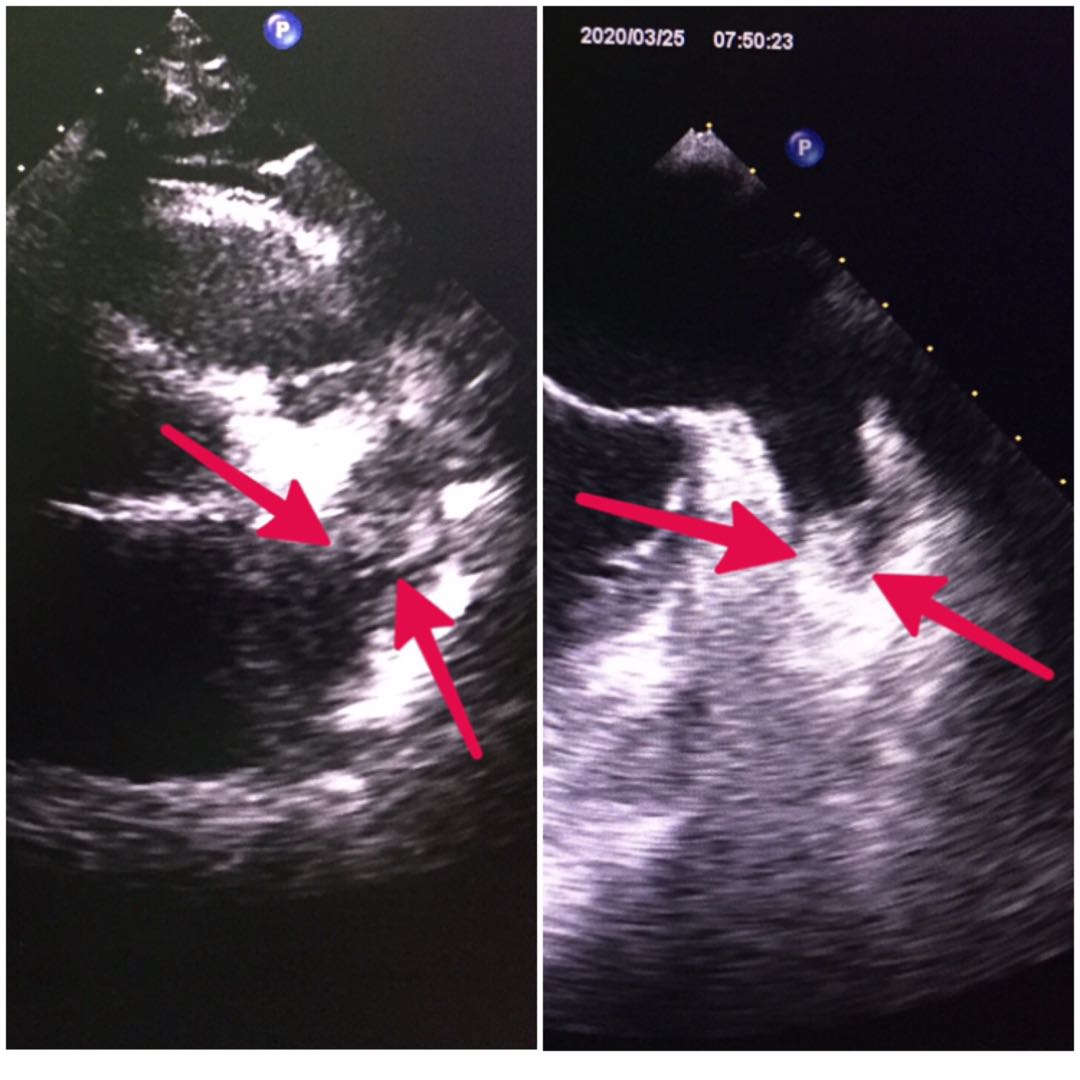

但在常规经胸超声心动图检查时发现,患者左心耳可疑稍高回声团(上图左),因心前区肺气等干扰,经胸超声心动图对左心耳的小血栓敏感性差,这一稍高回声团到底是不是血栓?诊断结果对下一步的治疗非常重要,如果是血栓,就有血栓脱落栓塞动脉的风险,比如栓塞大脑动脉造成脑梗。而临床上对于房颤患者左心耳血栓,需要进行抗凝治疗,但如果不是血栓,盲目进行抗凝治疗,会大大增加患者的出血风险。因此,只有明确是否存在血栓,才好开展下一步的治疗。

为此,超声二科主任危安在心内科的医生讨论沟通后,决定给王阿姨做个经食管超声检查。因是疫情期间,做食管超声会面临着很大的风险,检查前,科室按照医院新冠的筛查标准,给患者做了CT和核酸检测等,并做好了检查前、后诊室紫外线消毒等防控措施。4月13日,超声二科对患者进行了经食管超声扫查后发现,其左心耳的确有血栓(上图右)。在有了确凿的诊断后,心内科医师为患者制定了了个体化的诊疗方案。